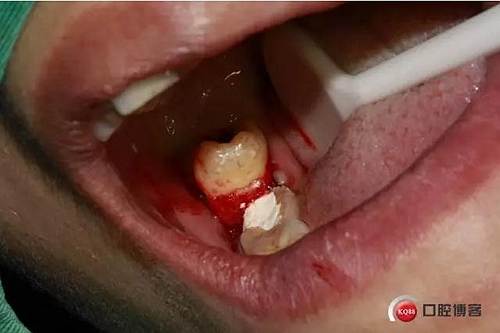

檢查:48號牙稍偏近中生長,周圍牙齦稍白,遠(yuǎn)中齦袋中有少許滲出物,探診;未出血,叩(--),冷熱(--)。47遠(yuǎn) 中未見齲壞,47冷熱(--)叩(--)。舌側(cè)少許齦上結(jié)石。X線檢查,48遠(yuǎn)中有陰影約2mm,根尖在神經(jīng)管內(nèi)約2--3mm。根尖未見陰影。

下面CBCT,可以看到兩個(gè)牙根的根尖三分之一在神經(jīng)管里面。

口內(nèi)照片,48遠(yuǎn)中三分之一覆蓋部分牙齦。